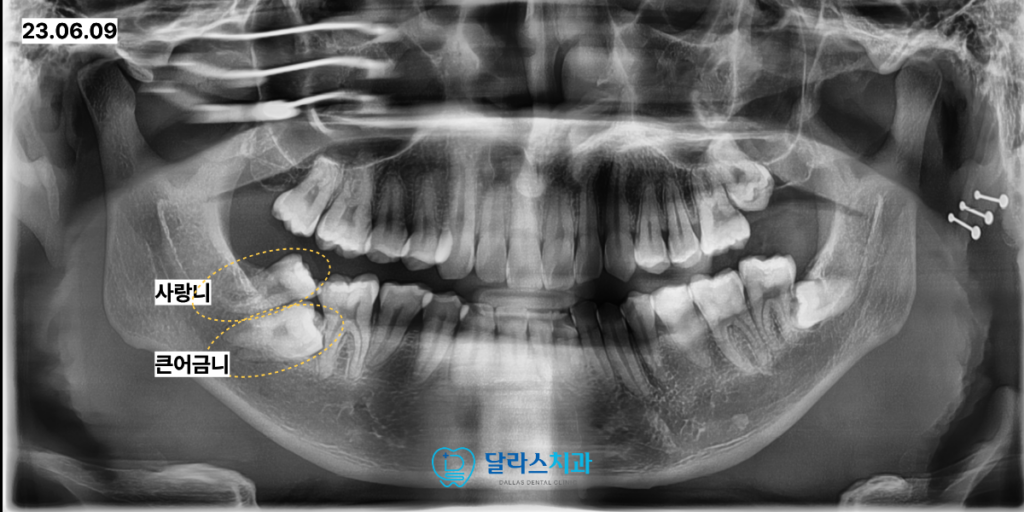

노원치과 달라스치과를 찾아주신 30대 남성 환자분께서는

오른쪽 아래 부위의 불편함 때문에 내원하셨습니다.

정밀 검사를 위해 촬영한 파노라마 사진을 분석한 결과

오른쪽 아래의 어금니가 사랑니에 갇혀 정상적으로 나오지 못한 매복 상태인 것이 확인되었습니다.

처음에 촬영을 해보았을 때는 사랑니가 큰 어금니보다 조금 더 위쪽에 위치하고 있어

겉으로 보기에는 해당 치아를 활용하는 것이 쉬워 보일 수 있는 상황이었습니다.

그러나 노원치과에서 치아의 회전 방향과 뿌리가 자리 잡은 위치를 면밀히 분석해 본 결과

사랑니를 발치하고 아래에 깊이 매복되어 있는 어금니를 뒤로 끌어올려 세우는 것이

장기적으로 훨씬 이로운 선택이라는 판단을 내렸습니다.